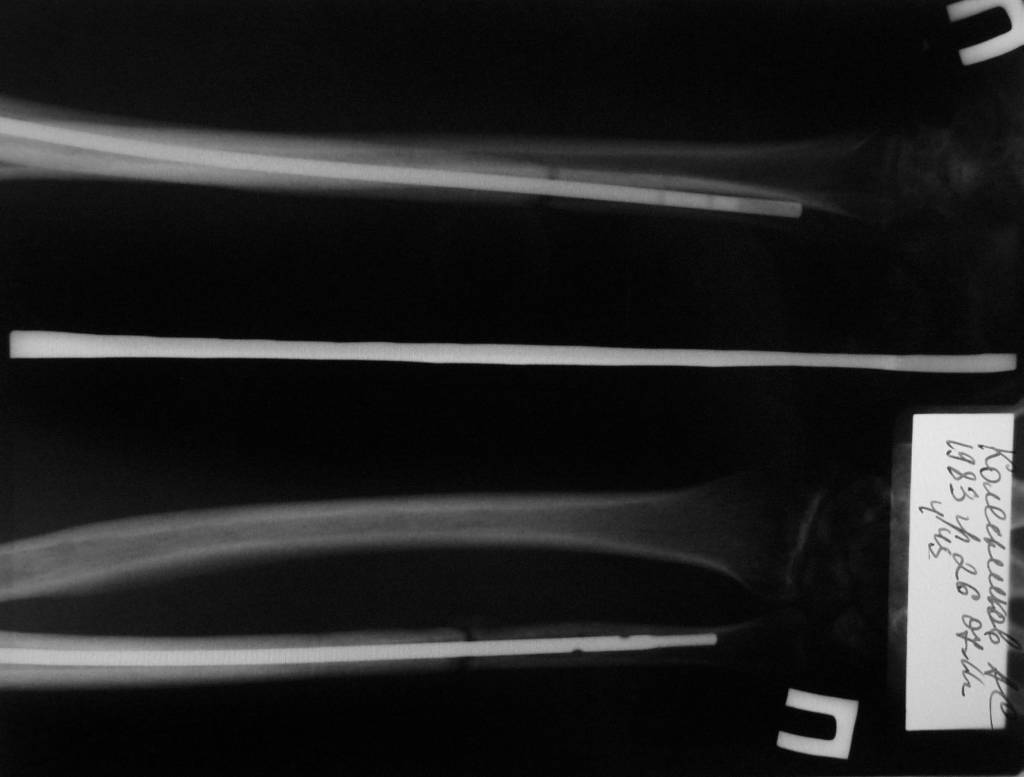

6 февраля 2011 года сломал локтевую кость со смещением. Поставили аппарат Илизарова. Вместо двух месяцев проносил четыре, срасталось медленно. Сняли, сказали разрабатывать и через 5 дней кость сместилась опять. 15 июня сделали вторую операцию, поставили дорогой стержень в кость, закрепили в области локтя на два шурупа. Перелом у меня в 1/3 ближе к кисти. Вторую часть кости одели на стержень, но не закрепляли. Также освежили концы костей, так как они зарубцевались и костномозговые каналы полностью закрылись.Месяц проносил лангету до плеча, потом сказали разрабатывать руку, но постепенно я начал чувствовать шевеление в месте перелома и щас чувствую.Щас опять хотят загипсовать уже всю руку на 2 месяца, но мне кажется что концы костей опять зарубцевались за 2 месяца зарастания "впустую" и даже в гипсе уже не срастется.По снимкам щель отчетливо видна. На руке вместе перелома нащупывается шишечка. Предположительно, что 1/3 кости, которая не прикручена к стержню, имеет хождение вдоль стержня.Кисти еще после аппарата Илизарова не поворачивается ладонью вверх и вниз. Имеет ход градусов 15 влево вправо и все.Что мне делать? Как еще восстановить руку? Еще одна операция? Исправит ли гипс на 2 месяца проблему? Мне 28 лет.

Вариантов действий несколько, 1)можно просто подождать (неизвестно сколько, и есть немалые шансы так и не дождаться),

2)можно наложить упрощенный аппарат на локтевую кость, чтобы сдавить поверх стержня,

3)стержень заменить на больший по диаметру, с возможностью компрессии,

4)заменить стержень на пластину с костной пластикой.

Оптимальны варианты 2 или 3. Наверно, есть смысл приехать к нам на очную консультацию.